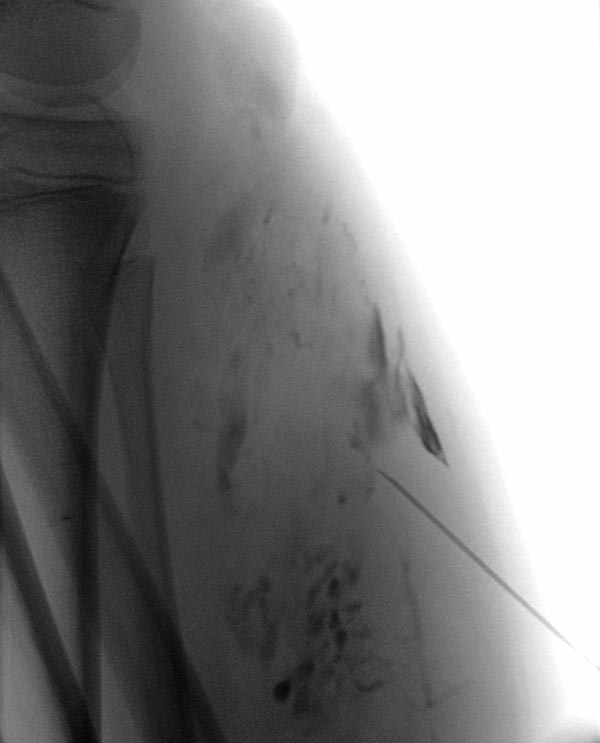

After additional puncture of a very distal part of the large-lumen communicating vein and contrast injection, there is no more outflow into the deep venous system. Thus, even in the long term, the risk of embolism of thrombi from the venous malformation into central conducting veins is eliminated.

Additional sclerotherapy 3 months after the first treatment with polidocanol foam 3% with ultrasound-guided direct puncture. The more proximal parts of the venous malformation are partially occluded, the still open channels of the venous malformation after the first treatment are significantly reduced in size. The former communication with the deep conducting venous system remains occluded. In the meantime, a temporary epiphysiodesis with temporary stapling of the growth plates had been performed for leg length correction on the other side.

A new puncture was performed more proximally on the lower leg because still open parts of the venous malformation were detectable here on ultrasound. After contrast injection, only a few, small-lumen areas of the venous malformation are contrasted. Sclerosing foam can be seen in the cavities of the distal part of the venous malformation (visible as intraluminal radiolucency).